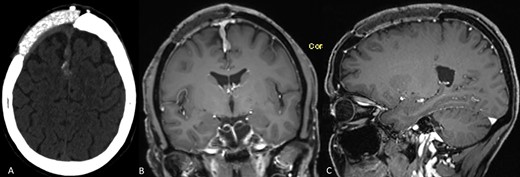

In 2012, the 45-year-old female patient presented at a neurosurgical department with aphasia and facial palsy. Magnetic resonance imaging (MRI) showed a large space-occupying tumor infiltrating the frontal bone. Consequently, the tumor was removed, and histological workup confirmed a benign meningioma WHO I. Two years later, a CAD/CAM non-resorbable biocompatible cranioplasty (BIOMET, Germany) composed of PMMA spherical macro beads, coated and fused with polyhydroxyethylmethacrylate, was implanted, see Fig. 1. Until February 2018, consecutive MRIs had shown a tumor-free area, and the clinical course had been uneventful. The MRI conducted in February 2018 and the subsequent MRI in June 2019 (Fig. 2A and B) showed a progressive contrast-enhancing mass along the falx cerebri that was strongly suspicious of recurrent meningioma. Therefore, revision surgery was recommended to remove the tumorous mass along the falx. Before surgery, computed tomography (CT) was carried out to visualize the bony attachments of the PMMA cranioplasty (Fig. 2C). Neither imaging modality had depicted any tumorous tissue inside the cranioplasty. Thus, preoperatively, the cranioplasty was not considered an area of tumor infiltration.

(A–C) Preoperative neuroimaging shows recurrent meningioma along the falx cerebri and under the cranioplasty (A: native CT scan, axial plane; B: contrast-enhanced MRI, coronal plane; C: contrast-enhanced MRI, sagittal plane).